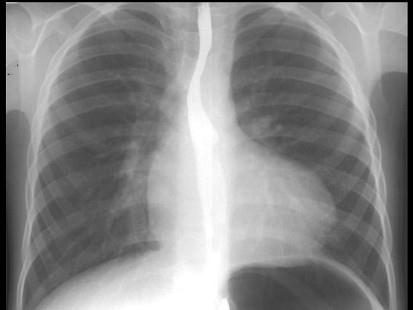

问题 如图,X线检查表现为肺动脉段凹陷,可能为下列哪一种先天性心脏病的 ( )

选项 A、室间隔缺损 B、动脉导管未闭 C、肺动脉狭窄 D、法洛四联症 E、房间隔缺损

答案 D